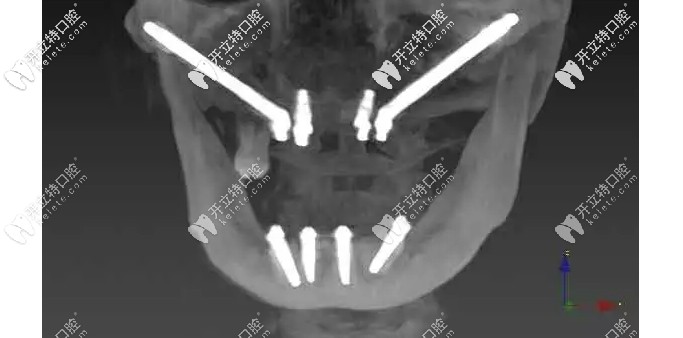

面對這種情況,想要做種植牙就要進(jìn)行穿顴種植,首先要了解顧客的身體情況;為了確保手術(shù)的能成功,需要制作3D打印頜骨模型,然后數(shù)碼設(shè)計(jì)術(shù)前導(dǎo)板......

術(shù)中,植體一段穿過顴骨另一端平放置在盡可能接近牙槽嵴頂?shù)奈恢?,且種植體有一個(gè)45°的轉(zhuǎn)角基臺(tái),就算在頜骨極度缺失的情況下,不植骨也可以馬上種植即刻修復(fù)哦!